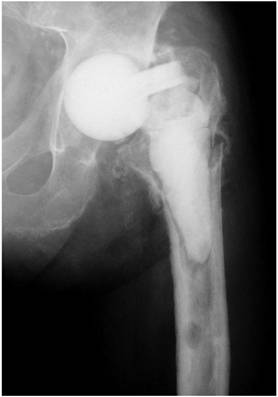

Depending on the particular cause, treatment options may strongly vary. In case of patient incompliance or inability to put partial weight bearing on the operated extremity, the patient should be rather considered as a candidate for a resection arthroplasty and not for a spacer implantation. For prevention of any spacer dislocation due to an insufficient fixation technique onto the proximal femur, a simple “press fit” method should be avoided (Figure 1). Alternatively, a partial (Figure 2) or normal cementation of the spacer into the femoral canal provides the advantage of rotational and axial stability [3]. A normal cementation has the disadvantage in comparison with the partial cementation that all cement debris have to be removed from the femoral canal during the later prosthesis reimplantation, and that during removal of the prosthesis stem osseous defects might occur. Recently, the “glove”-technique has been described as new method for femoral fixation of hip spacers [3]. This method provides a stable fixation onto the proximal femur at facilitating the spacer's explantation since the spacer can be removed at one piece and there is no need for removal of any cement debris compared with other normal cementation techniques.

Figure 1

Articulating hip spacer in situ, the spacer stem is inserted into the femur according to a “press-fit” method.